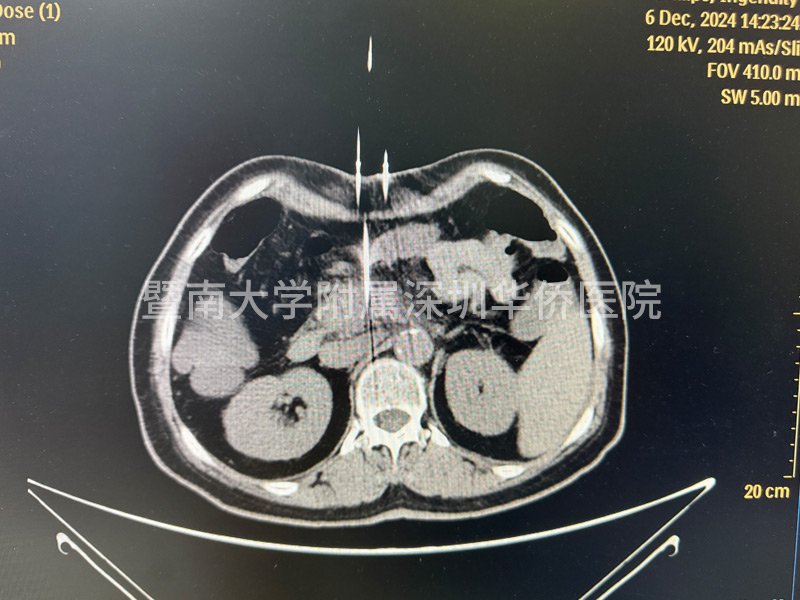

李女土的肿瘤在胰头位置,大小为2.8*3厘米,已经包绕肠系膜上动脉,失去了手术机会,在得知广东省应用了国产纳米刀治疗手术技术后,决定不远千里来到深圳华侨医院,接受纳米刀消融手术。

上午11点,李女士正式进入手术室,多位相关领域专家,通过国产研发的新型设备正式对李女士进行手术,纳米刀消融技术适合中晚期的胰腺癌的治疗,这台手术设备在产品设计中,具有全球领先的核心技术,实现了在消融过程中,电压恰到好处,作用于细胞膜磷脂双分子层,形成不可逆电穿孔,诱导细胞凋亡,激活细胞免疫,经过几个小时的奋战,李女士成功完成手术治疗,此次纳米刀消融手术,顺利开展完成!

在超声或CT引导下,纳米刀治疗系统能够精确计算出消融区域的形状和体积,并告知探针的有效消融范围。治疗计划精确到毫米级别,为患者提供个性化的治疗方案。